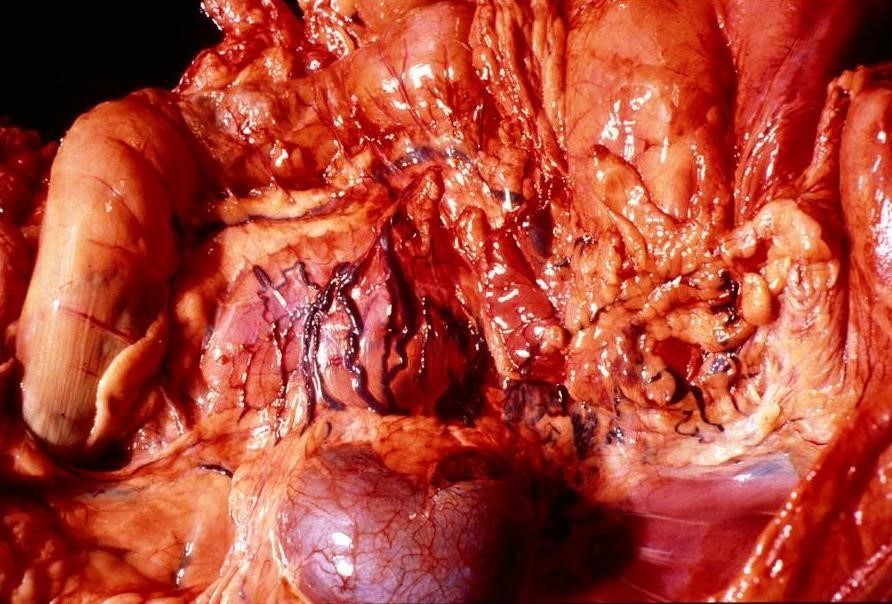

Describe this lesion

The normal anatomy of the thorax and abdomen of this cat has been severely disturbed, with the small intestine and other abdominal viscera being displaced cranially, presumably through the diaphragm.

Acute severe diffuse traumatic diaphragmatic herniation of the gastro-intestinal tract.